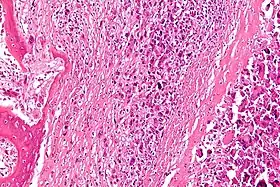

Обов'язково призначається рентгенограма кістки. Коли пухлина є, її видно на рентгенівських знімках. Різні новоутворення кісток, на рентгенівських знімках мають різні характеристики. Якщо ж по рентгенівському знімку важко визначити який процес протікає на ураженій ділянці кістки, то лікарі призначають МРТ (магнітно-резонансна томографія) і КТ (комп'ютерна томографія). Коли місце пухлини доступне, проводиться біопсія, тобто береться зразок тканини з новоутворення, що досліджується під мікроскопом.